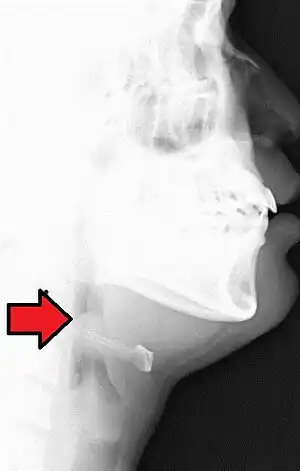

| Neck X-ray showing thumbprint sign. | |

Epiglottitis was historically mostly caused by infection by H. influenzae type b.[8] With vaccination it is now more often caused by other bacteria.[1] Other possible causes include burns and trauma to the area.[1] The most accurate way to make the diagnosis is to look directly at the epiglottis.[3] X-rays of the neck from the side may show a "thumbprint sign" but the lack of this sign does not mean the condition is absent.[1]

On lateral C-spine X-ray, the thumbprint sign describes a swollen, enlarged epiglottis.[11] A normal X-ray, however does not exclude the diagnosis.[11] An ultrasound may be helpful if specific changes are present, but its use as of 2018 is in the early stages of study.[11]